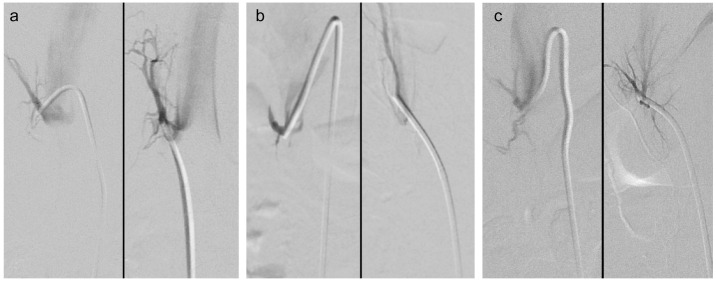

肾上腺静脉采样(AVS)失败通常是由于难以采样右肾上腺静脉(RAV)。正常情况下,小房室是尾侧定向的,然而,小房室的颅侧定向并不罕见。在这种情况下,使用多用途(MPA)导管形状可能有助于采样。2014年至2019年期间,351例患者接受了AVS和RAV采样,其中23例患者(7%,10M:13F)。收集AVS前成像、手术细节和AVS结果的数据,以IVC右侧壁为颅侧轴(0°定义为尾侧,180°定义为颅侧),在静脉造影中测量RAV垂直角度,并评估使用MPA导管成功取样前使用导管数量与各种手术措施的相关性。23例患者均在术中静脉造影时进行了颅面导向的AVS,技术上成功进行了24例AVS。在2例已知的颅向RAVs患者中,首选MPA导管。在其余患者中,21% (n= 5)的患者选择MPA导管作为第二选择,50% (n= 12)的患者选择MPA导管作为第三选择,最多的患者选择MPA导管作为第八选择(n=1)。早期使用MPA导管与较短的透视时间(R = 0.71, P = 0.0001)和较低的造影剂(R = 0.77, P < 0.0001)相关。这些结果支持MPA导管在颅向RAVs取样时的使用。当颅向RAV存在时,当尾向导管不能识别RAV时,应考虑使用MPA导管。

Adrenal vein sampling (AVS) failure is often attributed to difficulty sampling the right adrenal vein (RAV). Normally, the RAV is caudally oriented, however, cranial orientation of the RAV is not uncommon. In such cases, use of a multipurpose (MPA) catheter shape may facilitate sampling. Between 2014 and 2019, 351 patients underwent AVS and RAV sampling with an MPA catheter occurred in 23 patients (7%, 10M:13F). Data regarding pre-AVS imaging, procedural details, and AVS results were collected, the RAV vertical angle was measured on venography using the IVC right lateral wall as the craniocaudal axis (0° defined as caudal, 180° cranial), and correlation of the number of catheters used until successful sampling with the MPA catheter and various procedural measures was assessed. Twenty-four technically successfully AVS were performed in 23 patients, all of whom had cranially oriented RAVs on intra-procedural venography. An MPA catheter was the first choice in 2 patients with previously known cranially oriented RAVs. In the remaining patients, the MPA catheter was 2nd choice in 21% (n = 5), 3rd choice in 50% (n = 12), and up to 8th choice (n=1). Early utilization of the MPA catheter correlated with lower fluoroscopic time (R = 0.71, P = 0.0001) and lower contrast volume (R = 0.77, P < 0.0001). These results support the use of the MPA catheter when sampling cranially oriented RAVs. MPA catheters should be readily considered when cranially oriented RAVs are present and when caudally-oriented catheters fail to identify the RAV.